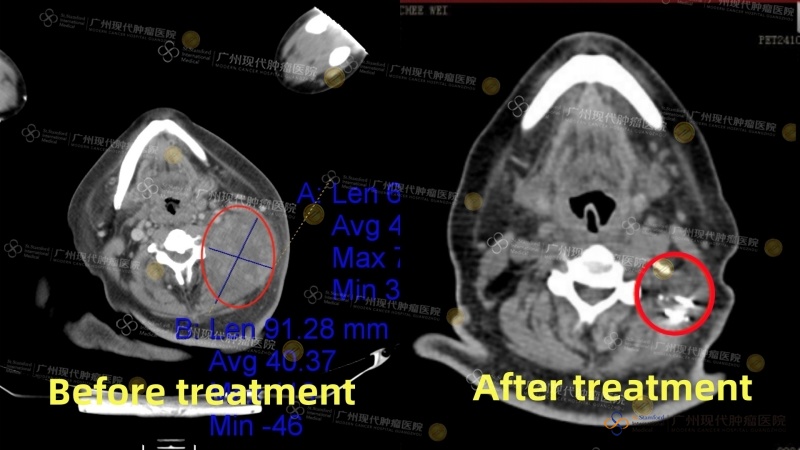

Tn. Chong Chee Wei dari Malaysia (kanker nasofaring) pada Oktober 2023 mengalami sakit kepala yang terus-menerus dan memutuskan untuk memeriksakan diri ke rumah sakit. Ia didiagnosis menderita kanker nasofaring stadium IV disertai metastasis ke kelenjar getah bening di leher, dengan diameter lesi terbesar mencapai 7,5cm. Di Malaysia, ia telah menjalani beberapa kali radioterapi dan kemoterapi, namun hasilnya kurang memuaskan. Berat badannya pun turun drastis sebanyak 30kg. Pada April 2024, ia datang ke Modern Cancer Hospital Guangzhou untuk menjalani pengobatan. Setelah menerima pengobatan komprehensif berupa terapi intervensi, terapi target, dan brachytherapy, tumornya menyusut hingga dua pertiga, dan kondisi fisiknya membaik secara signifikan. Kini, kondisi kesehatan Chong Chee Wei membaik secara nyata: tumornya mengecil secara drastis, berat badannya mulai naik kembali secara stabil, dan kondisi mentalnya juga pulih dengan baik.

Gambar perbandingan CT sebelum dan sesudah pengobatan Chong Chee Wei